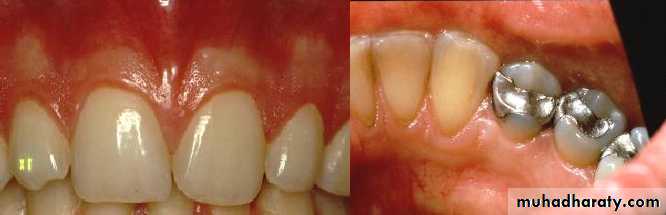

• Healthy vs. Diseased Tissues

• Normal

• Diseased• Color

• Pale pink ± pigmentation

• Acute: Red

• Chronic: bluish pink bluish red (cyanotic)

• contour

• Marginal gingiva Knife- edge margin ± stippling

• Follows a curved line about the tooth.

• Marginal gingiva: Rounded Rolled bulbous• Healthy vs. Diseased Tissues

• Periodontal Examination Diseased Periodontium• Inflamed Gingival Unit - Changes in Color, Contour and Consistency

• Inflamed Interdental Papillae and Rolled Gingival Margins• Periodontal Examination